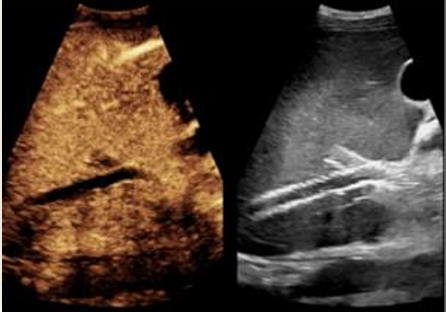

what phase is this

arterial or early vascular

portal venous phase

late vascular phase